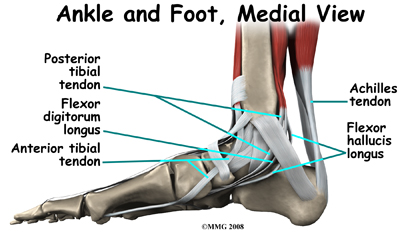

The large Achilles' tendon, at the back of the ankle, is one of the most important tendons for walking, running, and jumping. It attaches the calf muscles to the heel bone to allow us to rise up on our toes. The posterior tibial tendon attaches one of the smaller muscles of the calf to the underside of the foot. This tendon helps support the arch and allows us to turn the foot inward. Failure of the posterior tibial tendon is a major problem in many cases of AAFD.

The toes have tendons attached on the bottom of the foot that bend the toes down and also tendons that straighten the toes (on the top of the toes.) The anterior tibial tendon (tibialis anterior) allows us to pull the foot up, like you are taking your foot off the gas pedal. Two tendons, called the peroneal tendons, run behind the outer bump of the ankle (called the lateral malleolus.) These tendons help turn the foot outward.

The spring ligament complex is often involved in AAFD. This group of ligaments supports the talonavicular joint. The spring ligament complex works with the posterior tibial tendon and the plantar fascia to support and stabilize the longitudinal arch of the foot.

Dysfunction of the posterior tibial tendon has always been linked with AAFD. The loss of active and passive pull of the tendon alters the normal biomechanics of the foot and ankle.

At first you may notice pain and swelling along the medial (big toe) side of the foot. This is where the posterior tibialis tendon travels from the back of the leg under the medial ankle bone to the foot. As the condition gets worse, tendon failure may occur, and ligament laxity will worsen, causing the pain to get worse. Some patients also experience pain along the lateral (outside) edge of the foot and ankle, particularly as a deformity develops.